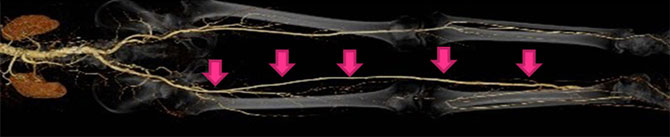

末梢動脈疾患に対する血行再建術

末梢動脈疾患に対するカテーテル治療では、国内でも有数の症例数を誇る当院循環器科と協力して、症例によっては末梢動脈へのバイパス手術を行っております。特に、膝下の病変に対するバイパス手術(Distal Bypass)は積極的に行っており、患者様の救肢ができるよう、最善の治療を行っております。

Distal Bypass:下腿への動脈バイパス手術

Distal Bypass:下腿への動脈バイパス手術